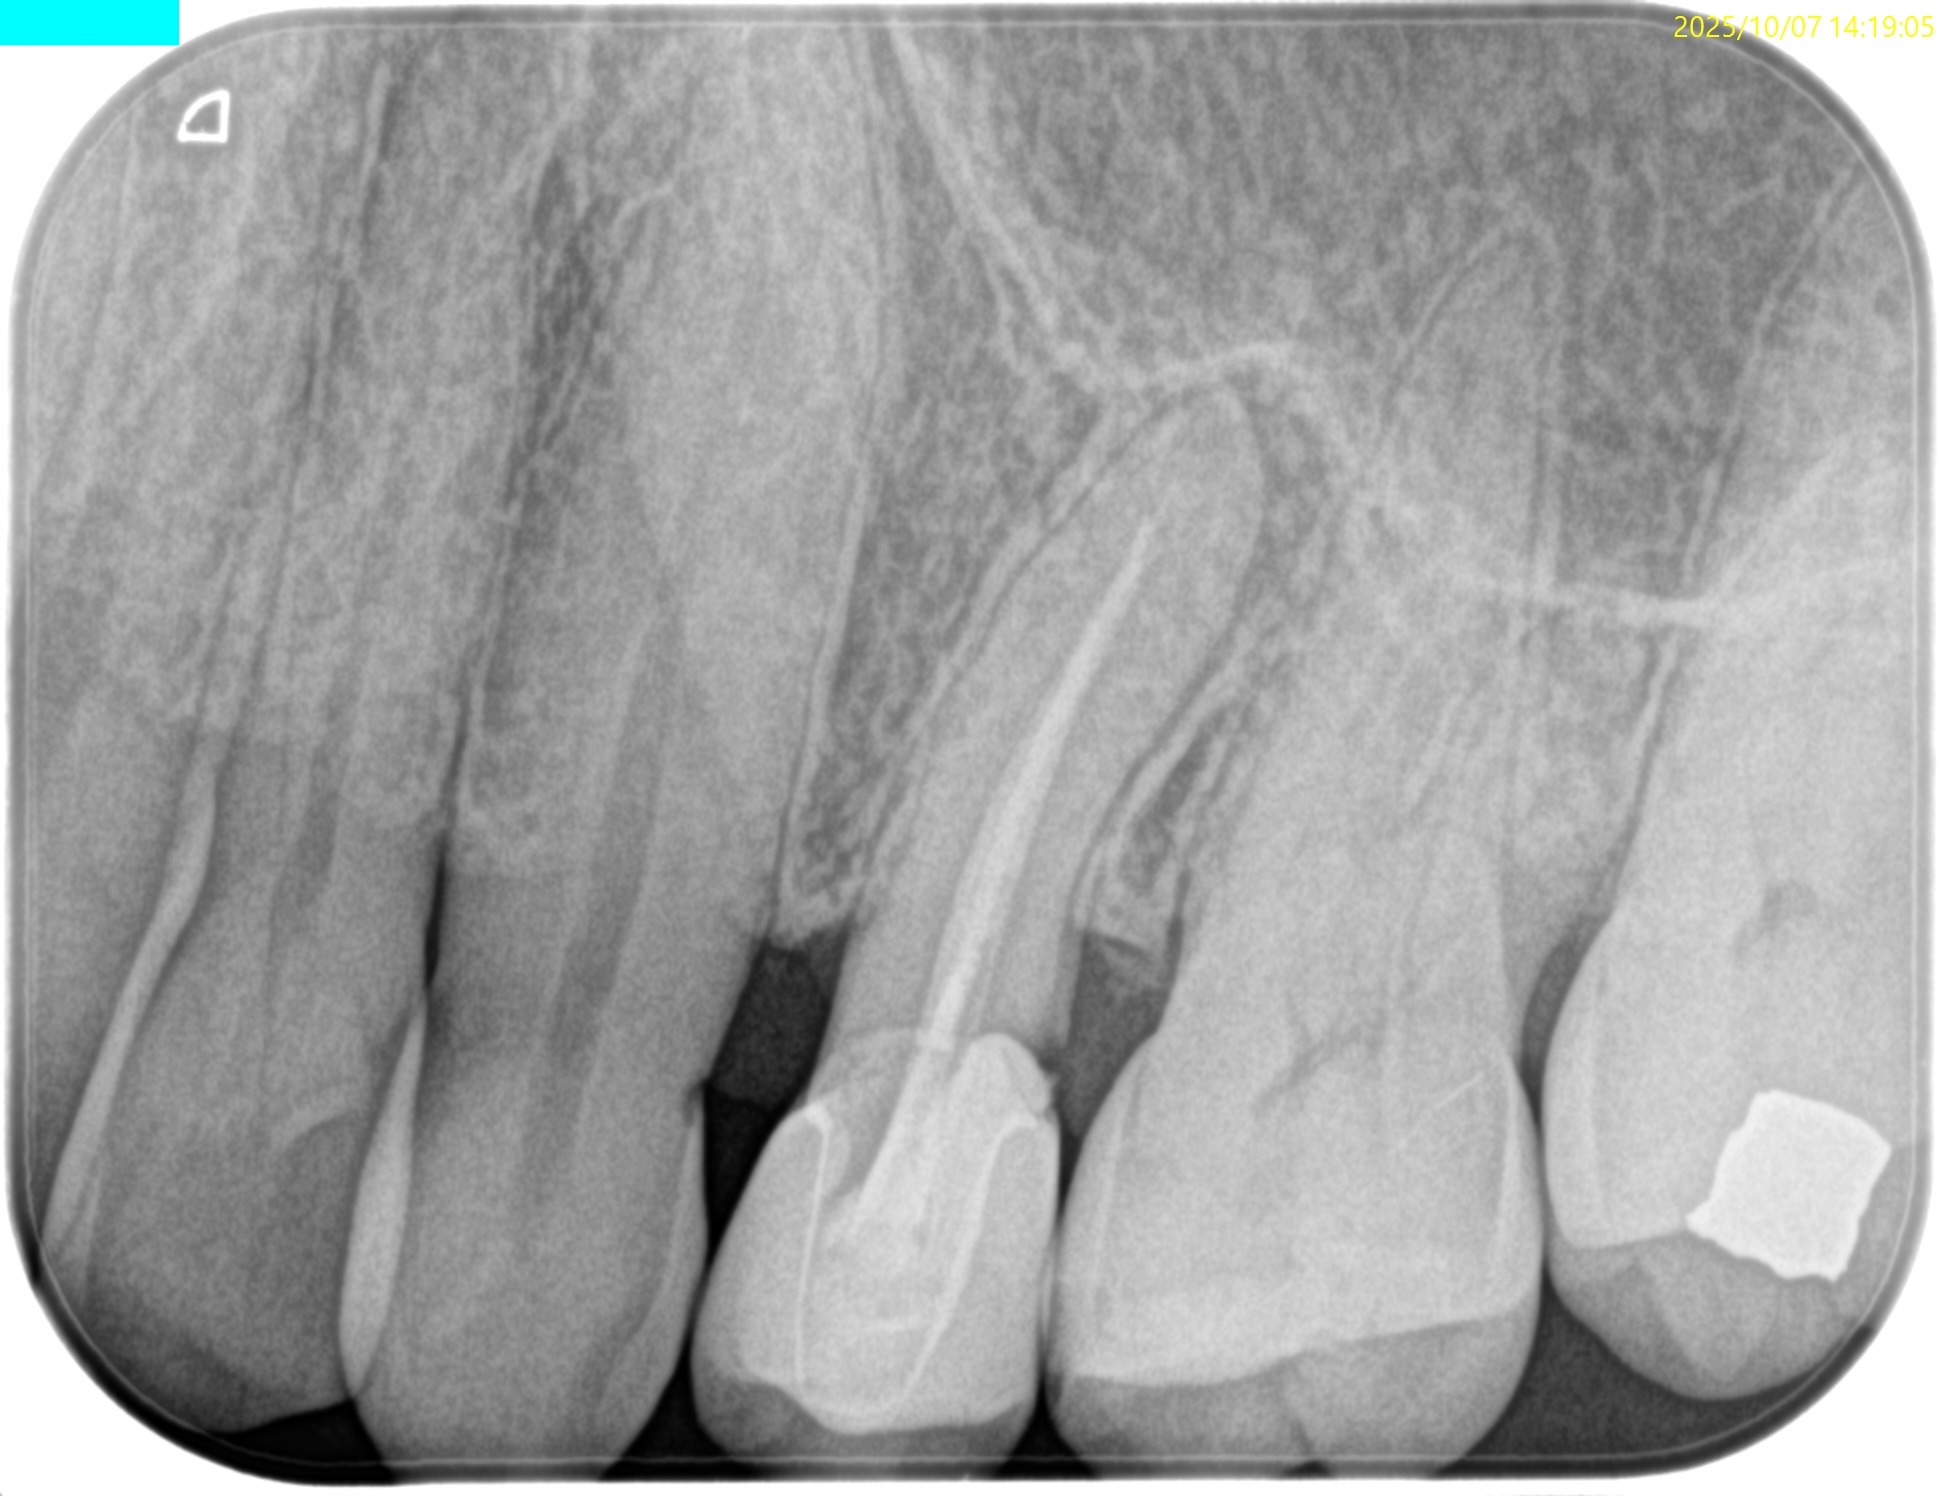

PA(2025.8.22)

もの詰まりはこの#13の遠心の築造体が剥き出しのマイクロリーケージであろう。

CBCT(2025.8.22)

#13 遠心のマージンが歯肉縁下でクラウンが不適合だ。ここにものが詰まるようだ。

これが患者さんの主訴である。